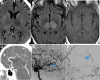

Figure 2.

A 52-year-old man with bithalamic edema from dural arteriovenous fistula (dAVF). A, An axial noncontrast computed tomography (CT) showing edema in both thalami, better depicted on the axial fluid attenuation inversion recovery (FLAIR) sequence (B). There is only mild associated enhancement on the postcontrast sequence (C). D, A sagittal maximum intensity projection image from a CT angiogram showing arterialized flow in the straight sinus. Early to mid arterial phase lateral digital subtraction angiography (DSA) from an internal carotid artery injection shows early venous drainage into the straight sinus (arrow, E). Lateral DSA from the external carotid artery injection more clearly shows early venous drainage into the straight sinus from a dAVF (F).